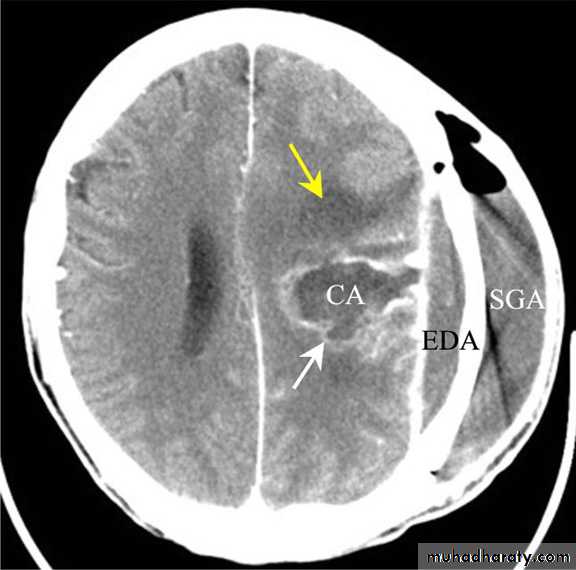

Bacterial Meningitis with suppuration

SUBDURALEMPYEMA

Subdural Empyemas

Source of infection:

Although uncommon, may develop following sinusitis or mastoiditis.

It carries a high mortality (5-10 %)

Pus is collected:

Over cerebral convexity.

In the parafalcine space.

Investigations:

• CT scanning;

Despite subdural empyema is a neurosurgical emergency, diagnosis is often delayed as the collection on CT is usually so slight and frequently missed.

2. MRI : useful when the diagnosis is doubtful.